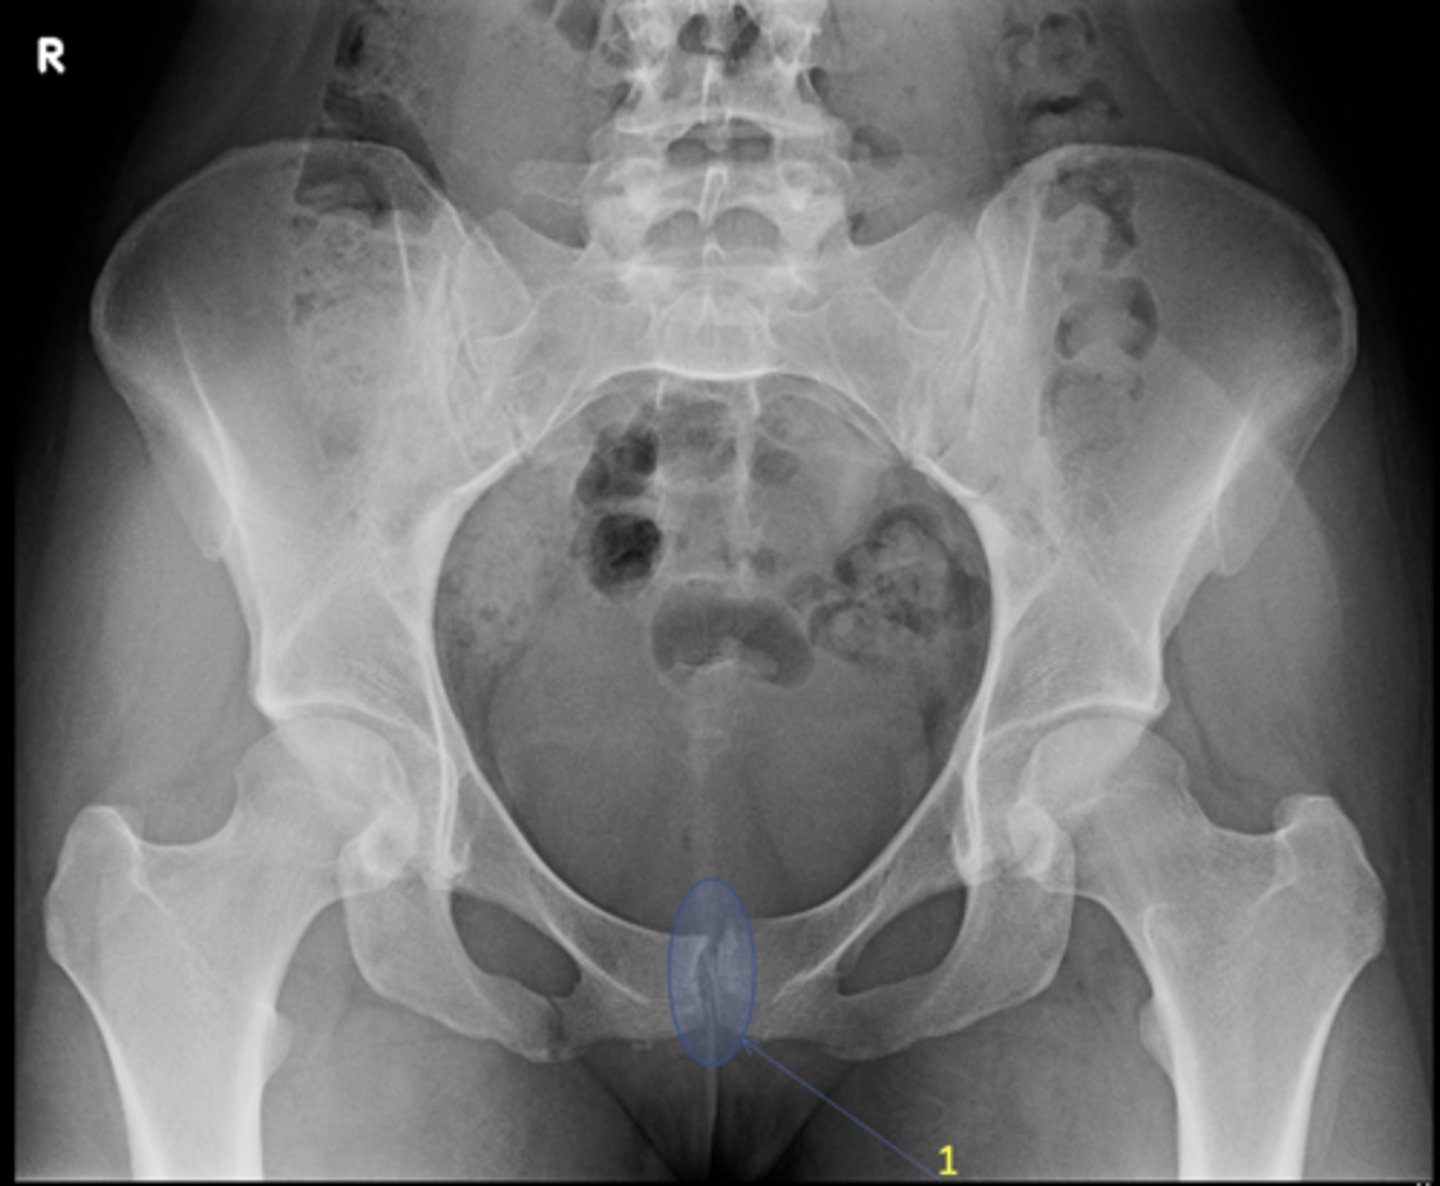

Symphysis pubis width

ID measurement

<p>ID measurement</p>

AP pelvis

What view is used to see the symphysis pubis width?

<p>What view is used to see the symphysis pubis width?</p>

Distance between opposing articular surfaces

Symphysis pubis width landmarks

<p>Symphysis pubis width landmarks</p>

8 mm

Maximum symphysis pubis width measurement in adults

<p>Maximum symphysis pubis width measurement in adults</p>

10 mm

Maximum symphysis pubis width measurement in children

<p>Maximum symphysis pubis width measurement in children</p>

Diastasis

Clinical significance of a widened symphysis pubis

<p>Clinical significance of a widened symphysis pubis</p>